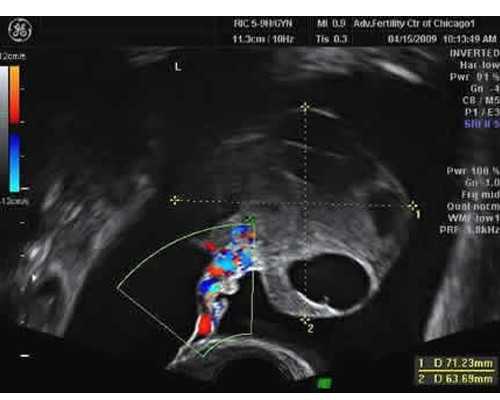

●试管助孕流程7步走● 第一步:控制超数排卵。需要采用控制性超数排卵来增强和改善卵巢功能,获得多个健康卵子,提供多个胚胎移植。 第二步:监测卵泡。当2-3个以上卵泡直径大于1.8cm,大于1.4cm的卵泡数等于E2值时,可注射人绒毛膜促性腺激素(HCG)促进卵泡成熟。 第三步:取卵。取卵的局部麻醉。阴道b超后,取卵针会穿过阴道穹窿到达卵巢,将卵子吸出。在显微镜下,立即将卵子转移到含有胚胎培养液的培养皿中,并置于37℃的培养箱中培养。 第四步:提取精华。在取卵的同一天取卵。取精前洗手,用手淫取精。拿的时候不要碰杯口或者杯内。 第五步:体外受精。取卵后4 ~ 5小时,将处理后的精子和卵子置于同一培养皿中,共培养18小时后,在显微镜下观察受精情况。 第六步:胚胎移植。受精卵体外培养48 ~ 72小时,可发育成8 ~ 16细胞期胚胎。 第七步:胚胎移植后的激素补充。一般胚胎移植后,常采用注射给黄体酮支持黄体。如果确定怀孕,将使用HCG补充至怀孕第10周。胚胎移植后14天,可通过尿检或抽血来确定是否怀孕。